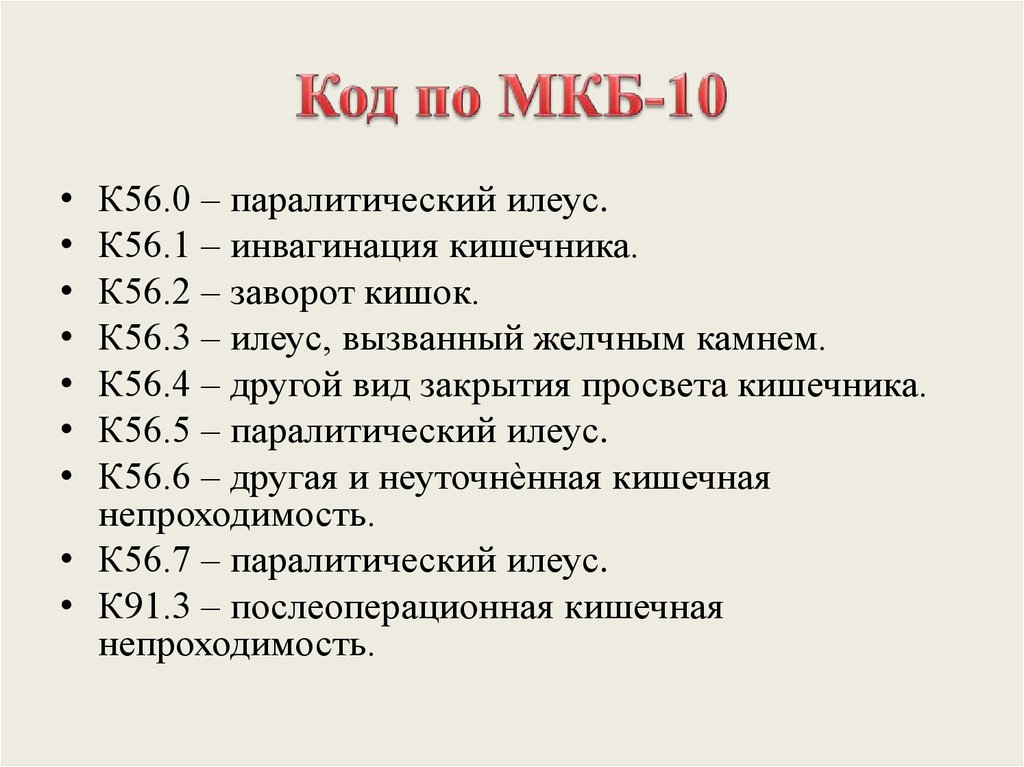

Код мкб 10 атерома головы

Код мкб 10 атерома головы 109 фото